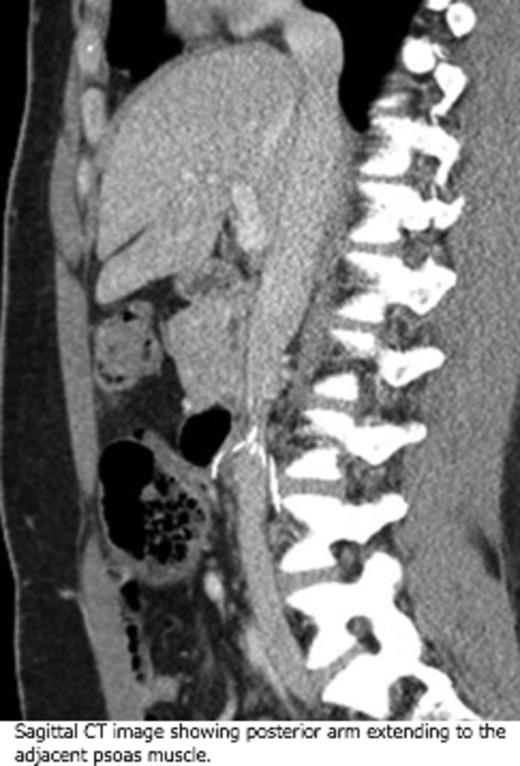

Results: (i) Case Description: A 38-year-old woman with a history of recurrent VTE presented with severe abdominal pain. Her initial left popliteal vein thrombosis and PE had occurred in 2000 after a few months on oral contraceptives (OC). She was treated with warfarin for a year. A recurrent unprovoked episode of left iliofemoral DVT was diagnosed four years later, at which time she was off OC. Indefinite warfarin treatment was started, given her young age and recurrent VTE. She became pregnant two years later and was switched to enoxaparin until two months after delivery. However, she did not restart warfarin and experienced no complications until three years later, when a prophylactic temporary IVC filter was placed prior to partial hysterectomy for menorrhagia. The surgery was performed without complications, but six months later she developed a recurrent untriggered right femoral DVT and began to experience sharp pains and an abrupt change in her bowel habits. At presentation, a CT scan (below) determined that her IVC filter had migrated out of position with its wires protruding into her aorta and spine and perforating her duodenum. Major abdominal and vascular surgery was performed to remove the filter. A thrombophilia panel returned with normal results. The patient was started on rivaroxaban indefinitely with no further issues.

Sagittal CT image showing posterior arm extending to the adjacent psoas muscle.